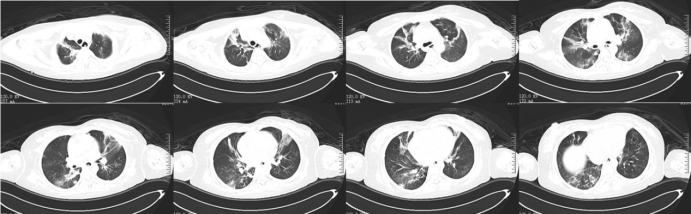

9月23日在ECMO支持下带患者外出行胸部CT检查:上肺渗出影斑片影双下肺实变,左下肺实变更明显(图7)

图片

7  患者胸部CT(2024-09-23)

928日外出复查胸部CT:双肺渗出和实变明显吸收改善(图10,图11)

10  复查胸部CT(2024-09-29)

11  患者胸部CT对比